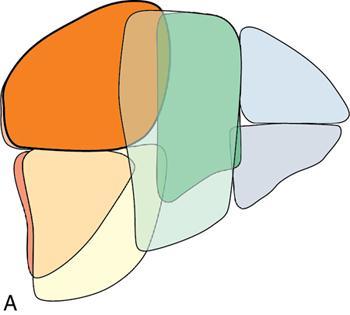

Ritu K. Kashikar, Shrinivas B. Desai Imaging is the mainstay of noninvasive diagnosis of the spectrum of abdominal pathologies or proving absence off thereof. Knowledge of normal anatomy and important normal variants is thus essential for the radiologist in order to avoid misinterpretation or erroneous diagnosis. This chapter highlights the normal anatomy of the hepatobiliary systems including the blood vessel and draining ducts and discusses relevant anatomical variants which may have important clinic implications. The liver is the largest abdominal organ, occupying the right upper abdominal quadrant and is in close approximation with the diaphragm, stomach and the gallbladder. It is largely covered by the costal cartilages. The liver is encapsulated by Glisson’s capsule which is a dense layer of connective tissue. It is covered by peritoneum, except in the regions of gallbladder fossa, fossa for inferior vena cava (IVC), and the bare area. The bare area is the posterocranial aspect of the liver, adjacent to the dorsal body wall, which is not covered by peritoneum. The liver has two surfaces, the convex diaphragmatic surface and a concave visceral surface. The slit in the hepatic hilum is called the porta hepatis and is penetrated by the right and left hepatic ducts (LHDs), hepatic artery and portal vein (PV). The distal portion of the lesser omentum is called the hepatoduodenal ligament and contains the common bile duct (CBD), hepatic artery, PV, nerves of liver and lymphatics. The liver has dual blood supply with hepatic artery providing 25% of hepatic blood and rest by portal vein (Fig. 9.2.1). Five ligaments connect the liver to the undersurface of the diaphragm. These include the falciform, the coronary and two lateral ligaments, all of which are peritoneal folds. The fifth ligament is a fibrous cord-like structure and represents the obliterated umbilical vein. The peritoneum invaginates into the liver parenchyma leading to formation of fissures. There are four normal fissures: fissures for the ligamentum teres, ligamentum venosum and gallbladder and the transverse fissure (Fig. 9.2.2). The liver is organized into microscopic functional units called lobules or acini. A central terminal hepatic venule surrounded by four to six terminal portal triads form a polygonal unit called the hepatic lobule. The terminal portal triad branches line the periphery of the unit. Between the terminal portal triads and the central hepatic venule the hepatocytes are arranged in one cell thick plates, surrounded by sinusoids. The blood flows from the terminal portal triad through sinusoids into terminal hepatic venule. Bile formed within the hepatocytes empties into terminal canaliculi which coalesce into the bile ducts (Fig. 9.2.3). This structure of the functional hepatic unit forms the basis of various functions of the liver. The normal relations of the liver are: The liver can be divided into right, left and caudate lobes. The right and left lobes are separated by the interlobular fissure and is oriented along a line passing through the gallbladder fossa inferiorly and the middle hepatic vein (MHV) superiorly (Fig. 9.2.4). This plane runs from the left of the IVC to the left of the gallbladder fossa and is a called the Cantlie’s line. Use of standardized, segmental anatomy is imperative because it facilitates communication and treatment planning. The segmental anatomy of liver is primarily based on vascular anatomy. The right lobe is divided into anterior and posterior sectors by of the right hepatic vein (RHV). The left lobe is divided into medial and lateraI sectors by an oblique plane connecting the left hepatic vein (LHV) and the falciform ligament. The liver is divided into upper and lower segments at the level of main portal vein (MPV) bifurcation (Fig. 9.2.5). Various systems are used in classification of liver anatomy. These are discussed in Table 9.2.1. The Couinaud’s system is the most commonly used and divides eight sections/segments which are discussed in details below (Table 9.2.2). 1. Segment 1 – Caudate lobe Bounded anteriorly and medially by the fissure for ligamentum venosum (Fig. 9.2.6). 2. Segment 2: Superior segment of the left lateral sector/section Bounded medially by falciform ligament and inferiorly by plane of MPV, also known as the posterior lateral sector (Bismuth, FCAT) (Fig. 9.2.7). 3. Segment 3: Inferior segment of left lateral sector/section Bounded medially by the falciform ligament and superiorly by the plane of the MPV bifurcation, also referred to as lateral anterior sector (Bismuth, FCAT) (Fig. 9.2.8). 4. Segment 4: Left medial sector/section Bounded laterally by falciform ligament and medially by Cantlie’s line (Fig. 9.2.9). 5. Segment 5: Inferior segment of the right anterior sector/section Bounded anteriorly by the gallbladder fossa and posteriorly by the plane of the RHV, superiorly bounded by the plane of MPV bifurcation (Fig. 9.2.10). 6. Segment 6: Inferior segment of the right posterior sector/section Bounded anteriorly by plane of the RHP and superiorly by the plane of the MPV bifurcation (Fig. 9.2.11). 7. Segment 7: Superior segment of the right posterior sector/section Bounded anteriorly by the plane of the RHV and inferiorly by the plane of the MPV bifurcation (Fig. 9.2.12). 8. Segment 8: Superior segment of the right anterior sector/section Bounded anteriorly by the plane of the gallbladder fossa and MHV, posteriorly bounded by the plane of the RHV and inferiorly by the plane of the MPV bifurcation (Fig. 9.2.13). Owing to its broad area of contact with the anterior abdominal wall, the liver is an ideal organ for evaluation with sonography. Ultrasound is commonly used for evaluation of size of the liver. On longitudinal scans obtained through the midhepatic line, if the liver measures 13 cm or less, it is normal in 93% of individuals (Fig. 9.2.14). The size of liver in various planes is discussed in chapter on normograms. When the area of contact between the liver and the anterior border of the right kidney, exceeds below two thirds of the kidney, the liver is considered as enlarged. The normal liver is homogeneous with fine echoes and appears evenly bright. The hepatic veins, PV and fissures interrupt the homogeneity of the liver parenchyma (Fig. 9.2.15). The parenchymal echogenicity may vary depending on the equipment, transducer and gain settings and should be judged by comparison with internal references like right renal cortex, body of the pancreas and PV walls. When compared with the adjacent normal right renal cortex the liver normally appears hyperechoic or isoechoic. The pancreas in a young individual is hypoechoic compared to the liver, and isoechoic in middle aged adults. As age progresses and fatty infiltration of the pancreas occurs, the pancreas appears hyperechoic to the liver. The liver is hypoechoic to the spleen. The normal liver reveals a density of 55–65 HU on nonenhanced scan and should appear homogenous with the exception of hypodensity in the regions of vessels and fissures. The liver parenchymal enhancement is minimal the arterial phase, with increase in density by only approximately 10 HU. This phase is usually to access vascular anatomy and to detect neovascular enhancing lesion like HCC, metastasis. Considering the fact that 75% of heptic venous supply is from the PV, the normal hepatic parenchyma shows maximum enhancement in the portal venous phase. During the venous/delayed phase the hepatic attenuation starts falling (Fig. 9.2.16). The hepatic fissures appear as linear fat containing structures. All the four fissures are well identifies on CT (Figs. 9.2.17–9.2.20). Normal liver should demonstrate uniform T1 signal similar or isointense to the paraspinal muscles and slightly hyper intense to the spleen. No signal drop should be seen on in or opposite phase. On T2W1 images liver appears slightly hyperintense to paraspinal muscles, isointense to pancreas and hypointense to spleen (Fig. 9.2.21). Following administration of extracellular contrast agents the normal liver parenchyma enhances on PV phase similar to that seen on CT. The arterial phase is preserved to determining vascular anatomy, variants and tumoural enhancement. Gadoxetic acid (Eovist) and gadobenate dimeglumine (MultiHance) are hepatobiliary agents showing excretion by the liver. In the case of gadoxetic acid, hepatic excretion is ~50%, which allows imaging in the hepatobiliary phase at ~20 minutes following injection. Gadobenate has only 3%–5% biliary excretion with hepatobiliary phase at approximately 40 minutes (Fig. 9.2.22). This property makes these agents useful in detection of nonhepatocyte containing lesions which appear hypointense to background liver on hepatobiliary phase. Hepatic anatomic variants are relatively common and represent normal interindividual variation of liver morphology. Normal Anatomic Variants Anatomic anomalies Accessory and pseudofissures may be seen in the liver. True accessory fissures result from infolding of the peritoneum usually along the undersurface of the liver and are rare. The inferior accessory fissure is the commonest accessory fissure and divides the posterior segment of the right hepatic lobe into lateral and medial portions. Diaphragmatic slips may cause indentation over the liver surface and are not commonly seen on imaging (Fig. 9.2.23). Leftward extension of the lateral segment of the left hepatic lobe appearing as a crescentic density that wraps around the spleen is referred to as sliver of liver. The left lobe of the liver may exhibit various forms: leaf like; spatular; truncated pyramid/wedge shaped; and a bifid appearance (Fig. 9.2.24). Elongated left lobe may be mimic splenomegaly, perisplenic hypoechoic collections or less commonly tumours. Imaging clues to diagnosis are establishing contiguity with liver and visualization of parenchymal vessels coursing through. The portion of the liver that extends medially from the right lobe between the IVC and fissure for ligamentum venosum is called the caudate lobe. The caudate lobe is divided inferiorly into a lateral caudate process and a medial papillary process. The medial papillary process projects medially towards the pancreatic head and has applied importance (Fig. 9.2.25). Riedel’s lobe is a tongue-like projection from the anterior aspect of the right lobe and the most common accessory lobe of the liver. It is seen most frequently in asthenic women. The reported prevalence of RL, ranges from 3.3% to 14.5% and the prevalence is higher in women than in men. It can be 20 cm or more in length and may extend up to the iliac fossa. It is usually asymptomatic and is discovered incidentally (Fig. 9.2.26). Accessory liver lobes are defined as a supernumerary lobe of normal hepatic parenchyma in continuity with the liver. This is a rare entity and usually occurs as a result of congenital ectopic hepatic tissue, although rarely may occur as a result of trauma or surgery. Various systems are proposed for classification of ALL. Another method of classification has been proposed based on biliary drainage and presence or absence of capsule. Accessory lobes can be readily diagnosed and characterized on CT or magnetic resonance imaging (MRI) done for related or unrelated conditions. CT shows the lesion as a soft–tissue density mass attached to the liver and isodense to the organ. The portal/hepatic venous branches can be seen coursing through it, in contiguity with the liver (Fig. 9.2.27). The coeliac axis trifurcates into common hepatic, splenic and left gastric arteries at the level of T12–L1. The common hepatic artery becomes the proper hepatic artery after origin of the gastro-duodenal artery. The hepatic artery proper ascends anterior to the PV and medial to the CBD and divides in to right and left hepatic artery (LHA). Occasionally the middle hepatic (segment 4) artery arises from hepatic artery proper. The hepatic artery appears as a tubular hypoechoic structure and shows antegrade flow on Doppler (Fig. 9.2.28). Normally the resistive index is low ranging between 0.55 and 0.7. The hepatic artery, its anatomy, branches, course, calibre are best evaluated on arterial phase of dynamic CT (Fig. 9.2.29). This is also the preferred modality prior to hepatobiliary surgical planning. Contrast-enhanced MRI also shows the above details but spatial resolution is lower. Road map of the arterial vascularity of the donor and recipient is a prerequisite for transplant surgery and complex hepatobiliary surgery. Detailed hepatic arterial anatomy and its variations have its significance in liver surgeries and interventional hepatic procedures, relative to the hepatic lobe involved. A classification method was described by Michel et al. in 1955, and is discussed in Table 9.2.3 (Fig. 9.2.30). I: standard anatomy ~60% (range 55%–61%) II: replaced LHA ∼7.5% (range 3%–10%) III: replaced RHA ~10% (range 8%–11 %) IV: replaced RHA and LHA ~1% V: accessory LHA from LGA ~10% (range 8%–11%) VI: accessory RHA from SMA ~5% (range 1.5%–7%) VII: accessory RHA and LHA ~1% VIII: accessory RHA and LHA and replaced LHA or RHA ~2.5% IX: CHA replaced to SMA ~3% (range 2%–4.5%) X: CHA replaced to LGA ~0.5% Other unclassified variants are: The two most common variants are the replaced right hepatic artery (RHA) arising from the SMA (Fig. 9.2.31) and replaced LHA arising from the left gastric artery (Figs. 9.2.32–9.2.34). Segment 4 artery – Middle hepatic artery (MHA) The middle hepatic artery usually arises from the LHA, it may, however, arise from the RHA (Fig. 9.2.35). The knowledge regarding origin of MHA is imperative in transplant surgery. The MHA can arise from RHA in Patients with replaced LHA. In patients with replaced RHA, the MHA arises from LHA (Fig. 9.2.36). Because of the considerable variability of hepatic arterial anatomy, assessment of this anatomy is crucial in the preoperative evaluation of potential living liver donors. Relevance of donor and recipient arterial anatomy is discussed in details in chapter on liver transplant. The relationship between the arterial variant and tumour is important to establish prior to major surgeries. Injuries to aberrant hepatic vessels and secondary ischaemic biliary strictures can be avoided. A replaced RHA has a more posterior course and long length. This variant may be advantageous in patients undergoing right lobar resection. However, there is greater propensity of involvement of replaced RHA by pancreatic head. The radiologist must be vigilant in reporting this variant (Fig. 9.2.37). Accessory RHA can, however, be sacrificed even if encased by neoplasm. An accessory LHA needs to be ligated separately in surgeries where blood supply in the porta hepatis is occluded. Replaced LHA from LGA maybe injured in case of surgeries at the level of hiatus. Hence this variant should be informed to surgeon in patients undergoing gastric surgeries. Preoperative mapping of the hepatic arterial anatomy prior to placement of intraarterial chemotherapy pumps is essential because it helps in deciding whether the candidate is suitable for the procedure and also if technical modifications are needed. The intraarterial infusion pump should be placed in the dominant hepatic artery as proximal as possible, but beyond GDA origin. Inpatients with standard anatomy, the pump is usually placed in the hepatic artery prior just after GDA origin. The location of pump can be modified in patients with variant anatomy, based on origin of GDA and dominant hepatic vessel. The PV is the main vessel in the portal venous system and drains blood from the gastrointestinal tract and spleen to the liver.